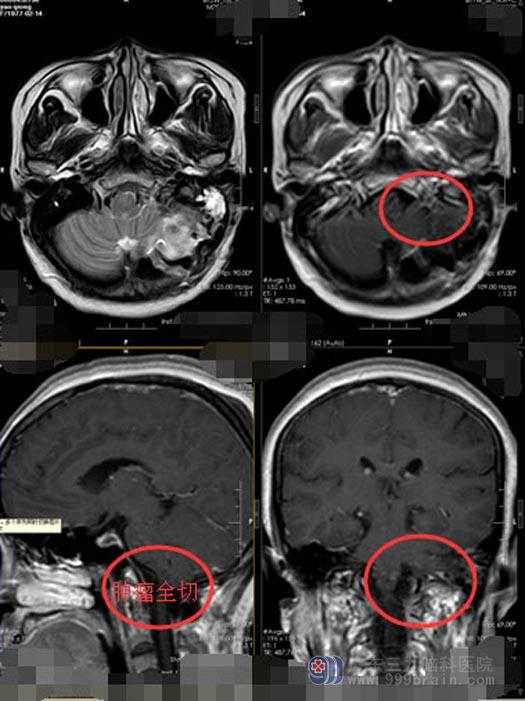

排除手术禁忌症后,由鲁明副院长主刀,神经外五科手术团队为姚阿姨施行“枕骨大孔区占位性病变切除术”。术中见灰白色肿瘤组织位于小脑内,内侧挤压脑干,显微镜下小心分离保留重要血管,可见其血供丰富,术中肿瘤全切。术后第二天,姚阿姨生命体征平稳,神志清楚,对答正确,四肢肌力肌张力正常,可遵嘱活动,无任何神经功能障碍与并发症,复查MR示:肿瘤全切,病理检验结果:枕骨大孔区纤维型脊膜瘤,WHO I 级,部分区域细胞增生活跃。经过二十多天的住院检查和治疗,目前已康复出院。